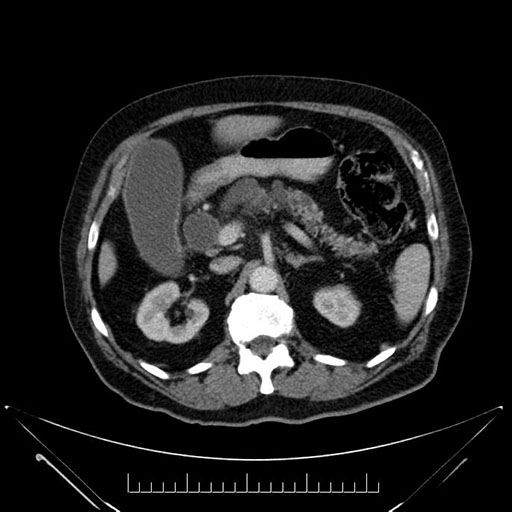

Whipple (pancreaticoduodenectomy) [case 7]

Axial - 3 months prior